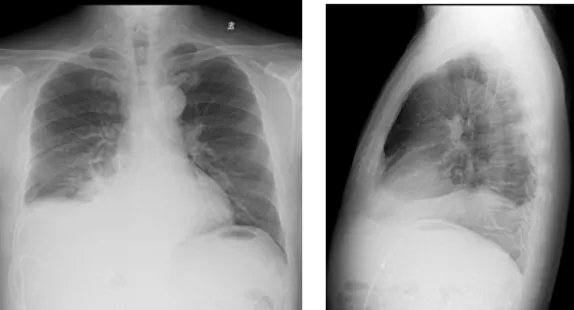

影像學檢查結果

image.png

右肺炎癥不能排除,請結合臨床。右側少量胸腔積液